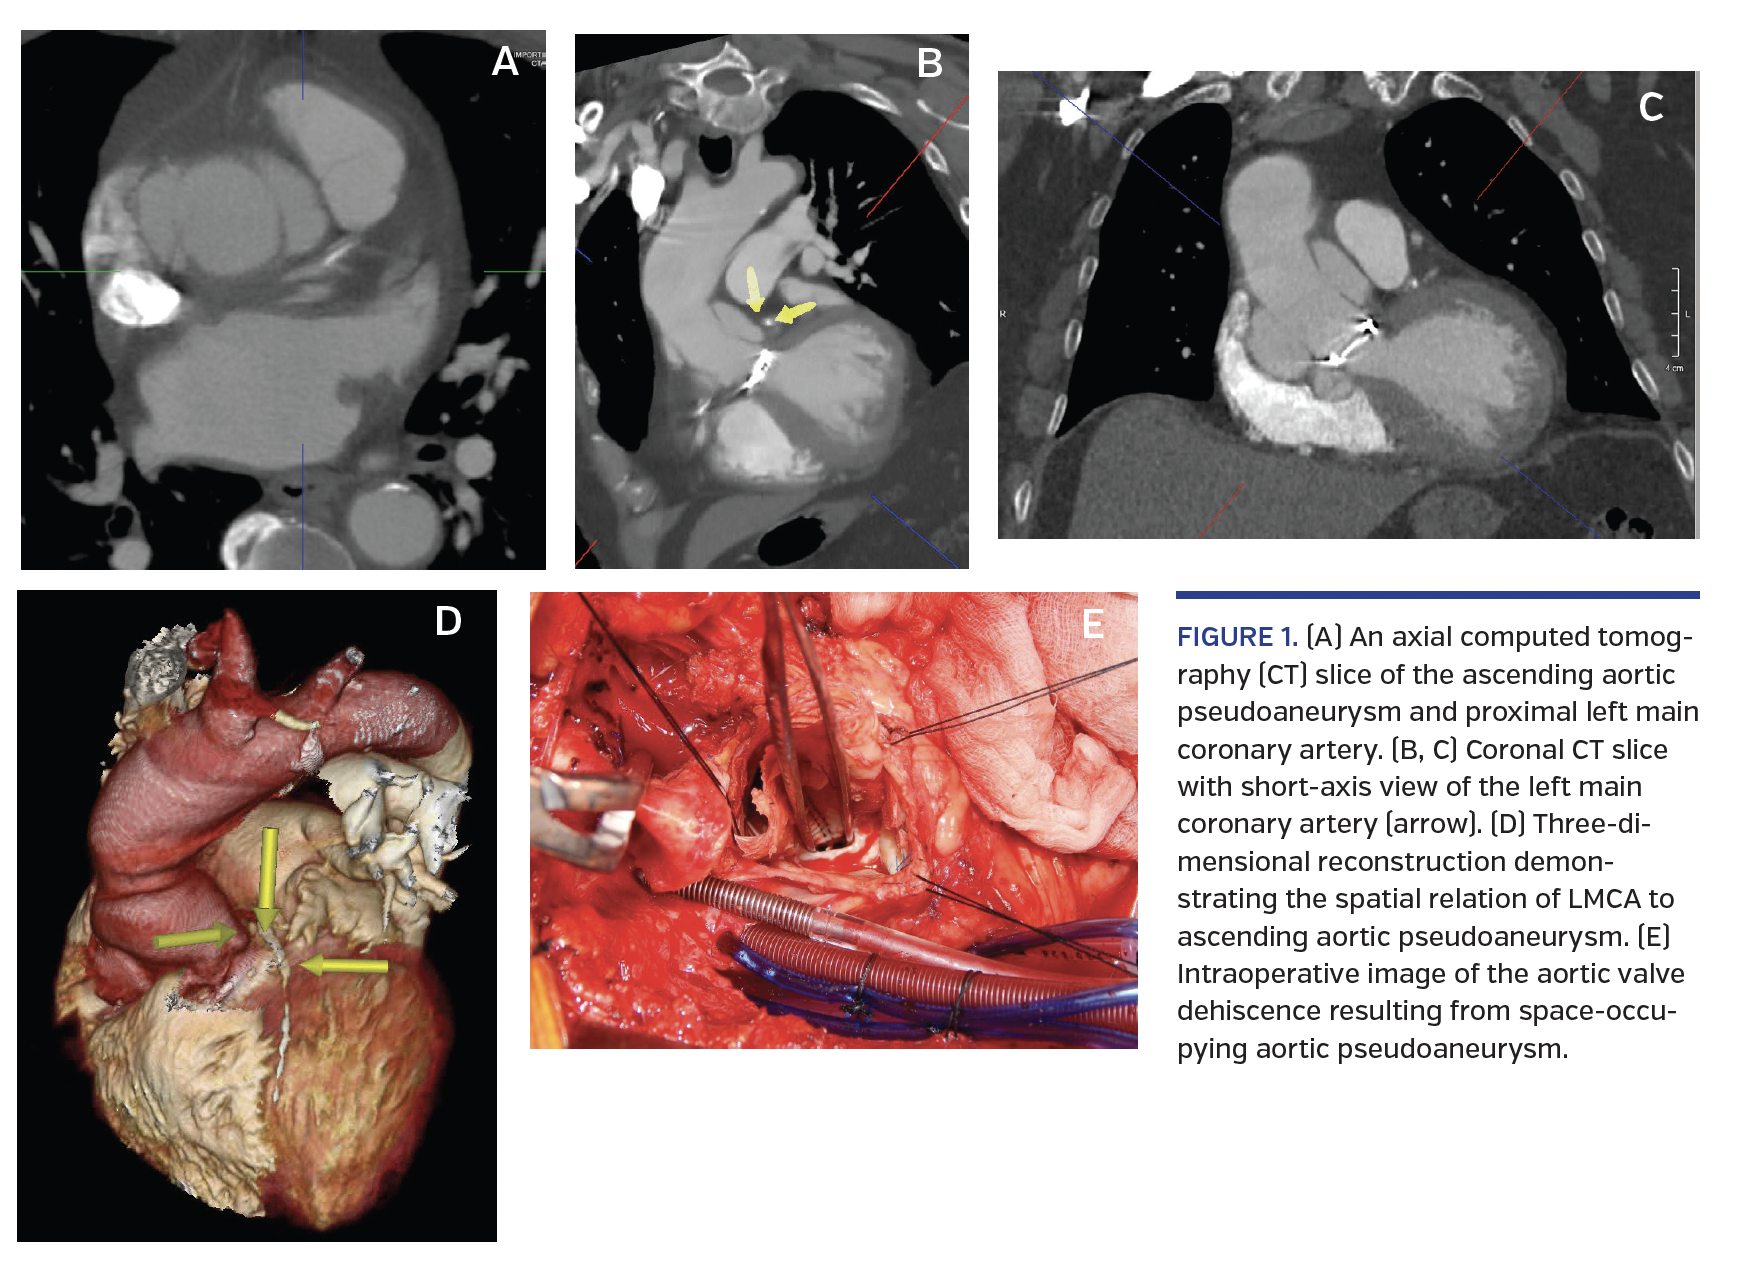

A 75-year-old man with a history of mechanical aortic valve replacement (AVR) with aortic conduit for severe aortic insufficiency underwent routine computed tomography (CT) evaluation revealing right coronary anastomosis endoleak and proximal aortic root pseudoaneurysm. The aortic dilation had been identified after the index surgery and was serially monitored. However, the follow-up CT scan revealed accelerated dilation with a 0.5 cm enlargement in 6 months. CT chest revealed close proximity of the aortic pseudoaneurysm with the ostium of the left main coronary artery (LMCA) resulting in intermittent compression (Figures 1A and 1B). Transthoracic echocardiography (TTE) revealed flow within an outpouching surrounding the proximal aortic root consistent with pseudoaneurysm. Pre-repair coronary angiography showed intermittent compression of the LMCA (Figures 2 and 3; Videos 1 and 2). The patient subsequently underwent bioprosthetic aortic valve repair with aortic conduit and re-implantation of the right and left coronary arteries due to dehiscence of the mechanical aortic valve (Figures 1C and 1D). Postoperative angiography demonstrated resolution of the aortic pseudoaneurysm and the associated LMCA compression.